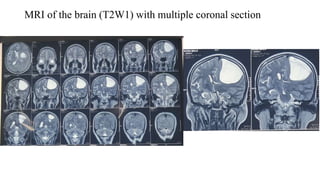

MRI of the brain (T2W1) with multiple coronal section

MRI of thebrain (T2W1) with multiple coronal section

• #46 In coronal view the lesion pused the adjacent to left lateral ventricle medially and inferiorly.